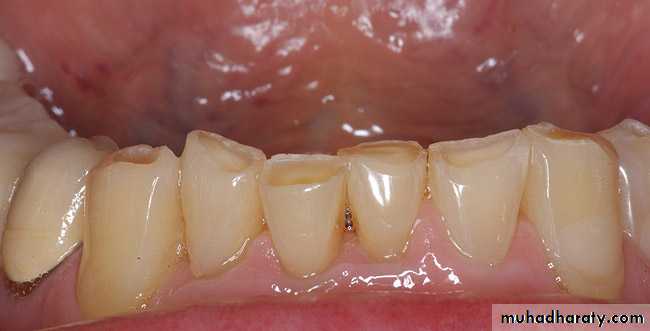

incipient caries.

cervical erosion and occlusal (incisal)attrition

enamel fractures resulting in exposure of dentinal tubules can cause reversible pulpitis.Symptoms